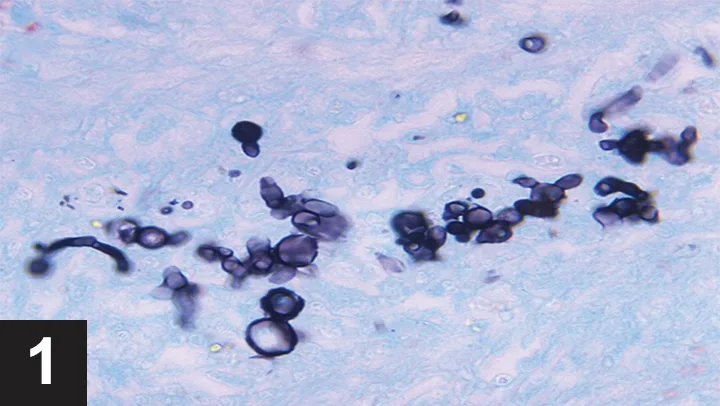

The owner consented to further testing, and a radiographic pattern consistent with pulmonary blastomycosis was identified on thoracic radiographs (Figure 2). Ocular examination was unremarkable. Mild leukocytosis and monocytosis were evident on CBC, while the serum chemistry panel was unremarkable. A urine sample was submitted for Blastomyces dermatitidis enzyme immunoassay (EIA) for additional confirmation, and treatment with itraconazole was started.

FIGURE 2

Thoracic radiograph of a dog with blastomycosis. Note the nodular interstitial pattern with patchy alveolar infiltrates. Image courtesy Dr. Shawn MacKenzie